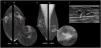

The nodular form is seen in patients with gynecomastia for less than 1 year.11 It is often referred as the early florid phase. Histologically, nodular gynecomastia is characterized by prominent ductal hyperplasia and cellular/proliferative stroma.4 It is worth noting that nodular gynecomastia is reversible if the underlying cause(s) is eliminated.4 Mammographically, it manifests as a nodular or fan-shaped subareolar opacity.4 On ultrasound, it appears as a disk-shaped, hypervascular, hypoechoic subareolar nodule surrounded by breast tissue 4,11 (Figs. 2 and 3).

60 year-old men with personal history of lung cancer presented with a left retroareolar lump and clear ipsilateral nipple discharge. On the low energy images (A, C), a nodular left subareolar opacity is seen. On the recombined images (B, D), it shows no enhancement. Sonographically (E), it corresponds to a hypoechoic subareolar nodule surrounded by breast tissue. Asymmetrical gynecomastia is also evident on CT images (F). Findings are suggestive of nodular pattern gynecomastia.

60 year-old male, HIV positive, presented with a right retroareolar mass and clear nipple discharge. No lymphadenopathies on physical exam. On the low energy right CC image (B), a nodular subareolar image can be seen. On the recombined images (A, C), a progressive mass enhancement is depicted. Note the increased in conspicuity at the last performed view (R-ML). On ultrasound (D), a hypoechoic subareolar nodule surrounded by breast tissue is shown. A 14G core needle biopsy confirmed the diagnosis of nodular gynecomastia.